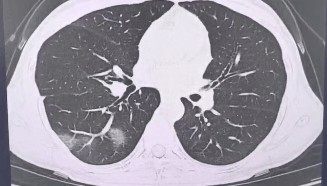

查出流感没在意,女子硬扛三天后肺都“白”了……

流感不过是一场“重感冒” 吃点药休息休息就能好? 浙江杭州39岁的程女士(化姓)是名“工作狂”, 经...